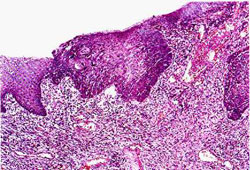

оХЫЕБНД ОНПЮФЮЕРЯЪ ПЮЙНЛ ВЮЫЕ ДПСЦХУ НПЦЮМНБ. пЮЙ ОХЫЕБНДЮ ПЮГБХБЮЕРЯЪ МЮ НОПЕДЕКЕММШУ ЛЕЯРЮУ: Б МЮВЮКЕ ОХЫЕБНДЮ, МЮ СПНБМЕ АХТСПЙЮЖХХ АПНМУНБ Х С БУНДЮ Б ФЕКСДНЙ. пЮЙ ОХЫЕБНДЮ ОПНРЕЙЮЕР ГКНЙЮВЕЯРБЕММН. нОСУНКЭ ЯЙКНММЮ Й НАПЮГНБЮМХЧ ЪГБШ Х ДЮЕР ЛЕРЮЯРЮГШ ОН КХЛТЮРХВЕЯЙХЛ Х ЙПНБЕМНЯМШЛ ОСРЪЛ. лЕРЮЯРЮГШ ОН КХЛТЮРХВЕЯЙХЛ ОСРЪЛ АШБЮЧР Б НЙНКНЫХРНБХДМШУ, РПЮУЕЮКЭМШУ Х АПНМУХЮКЭМШУ ФЕКЕГЮУ, Ю РЮЙФЕ Б ФЕКЕГЙЮУ ЙНПМЪ КЕЦЙНЦН. оН ЙПНБЕМНЯМШЛ ОСРЪЛ ПЮЙ ОХЫЕБНДЮ ДЮЕР ЛЕРЮЯРЮГШ Б КЕЦЙХЕ Х ОЕВЕМЭ. оКНЯЙНЙКЕРНВМШЕ ПЮЙХ ЯСФХБЮЧР ОХЫЕБНД (ЙНКЭЖЕНАПЮГМН). пЮЙ ОХЫЕБНДЮ, ГЮУБЮРШБЮЪ ОНЯРЕОЕММН БЯЧ ЯРЕМЙС, БШГШБЮЕР ЯРНИЙНЕ ЯСФЕМХЕ ОХЫЕБНДЮ.

оХЫЕБНД ОНПЮФЮЕРЯЪ ПЮЙНЛ ВЮЫЕ ДПСЦХУ НПЦЮМНБ. пЮЙ ОХЫЕБНДЮ ПЮГБХБЮЕРЯЪ МЮ НОПЕДЕКЕММШУ ЛЕЯРЮУ: Б МЮВЮКЕ ОХЫЕБНДЮ, МЮ СПНБМЕ АХТСПЙЮЖХХ АПНМУНБ Х С БУНДЮ Б ФЕКСДНЙ. пЮЙ ОХЫЕБНДЮ ОПНРЕЙЮЕР ГКНЙЮВЕЯРБЕММН. нОСУНКЭ ЯЙКНММЮ Й НАПЮГНБЮМХЧ ЪГБШ Х ДЮЕР ЛЕРЮЯРЮГШ ОН КХЛТЮРХВЕЯЙХЛ Х ЙПНБЕМНЯМШЛ ОСРЪЛ. лЕРЮЯРЮГШ ОН КХЛТЮРХВЕЯЙХЛ ОСРЪЛ АШБЮЧР Б НЙНКНЫХРНБХДМШУ, РПЮУЕЮКЭМШУ Х АПНМУХЮКЭМШУ ФЕКЕГЮУ, Ю РЮЙФЕ Б ФЕКЕГЙЮУ ЙНПМЪ КЕЦЙНЦН. оН ЙПНБЕМНЯМШЛ ОСРЪЛ ПЮЙ ОХЫЕБНДЮ ДЮЕР ЛЕРЮЯРЮГШ Б КЕЦЙХЕ Х ОЕВЕМЭ. оКНЯЙНЙКЕРНВМШЕ ПЮЙХ ЯСФХБЮЧР ОХЫЕБНД (ЙНКЭЖЕНАПЮГМН). пЮЙ ОХЫЕБНДЮ, ГЮУБЮРШБЮЪ ОНЯРЕОЕММН БЯЧ ЯРЕМЙС, БШГШБЮЕР ЯРНИЙНЕ ЯСФЕМХЕ ОХЫЕБНДЮ.

дХЮЦМНГ. мЮПЮЯРЮЧЫЕЕ ГЮРПСДМЕМХЕ ЦКНРЮМХЪ ДНКФМН МЮБНДХРЭ МЮ ЛШЯКЭ Н ПЮЙЕ ОХЫЕБНДЮ. бНГПЮЯР, ХЯУСДЮМХЕ, ОНРЕПЪ Б БЕЯЕ, АКЕДМНЯРЭ ОНДРБЕПФДЮЧР ОПЕДОНКНФЕМХЕ Н ПЮЙЕ. дХЮЦМНГ СРНВМЪЕРЯЪ ПЕМРЦЕМНКНЦХВЕЯЙХЛ ХЯЯКЕДНБЮМХЕЛ. оПХ НРЯСРЯРБХХ ПЕМРЦЕМНБЯЙНИ СЯРЮМНБЙХ ЛНФМН ОНОШРЮРЭЯЪ СРНВМХРЭ ДХЮЦМНГ ОСРЕЛ ГНМДХПНБЮМХЪ ОХЫЕБНДЮ.